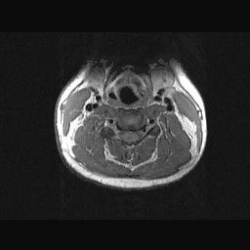

MRT durch den Hals.

Durch den Hals verlaufen verschiedene Versorgungsstränge wie Speiseröhre, Luftröhre und Blutbahnen. Das Knochengerüst (Halswirbelsäule) muss eine möglichst große Flexibilität für den Kopf herstellen. Der vordere Teil des Halses, der den Kehlkopf und den Schlund enthält, wird als Gurgel bezeichnet (von lateinisch: gurgulio = Schlund, Kehle, Luftröhre).